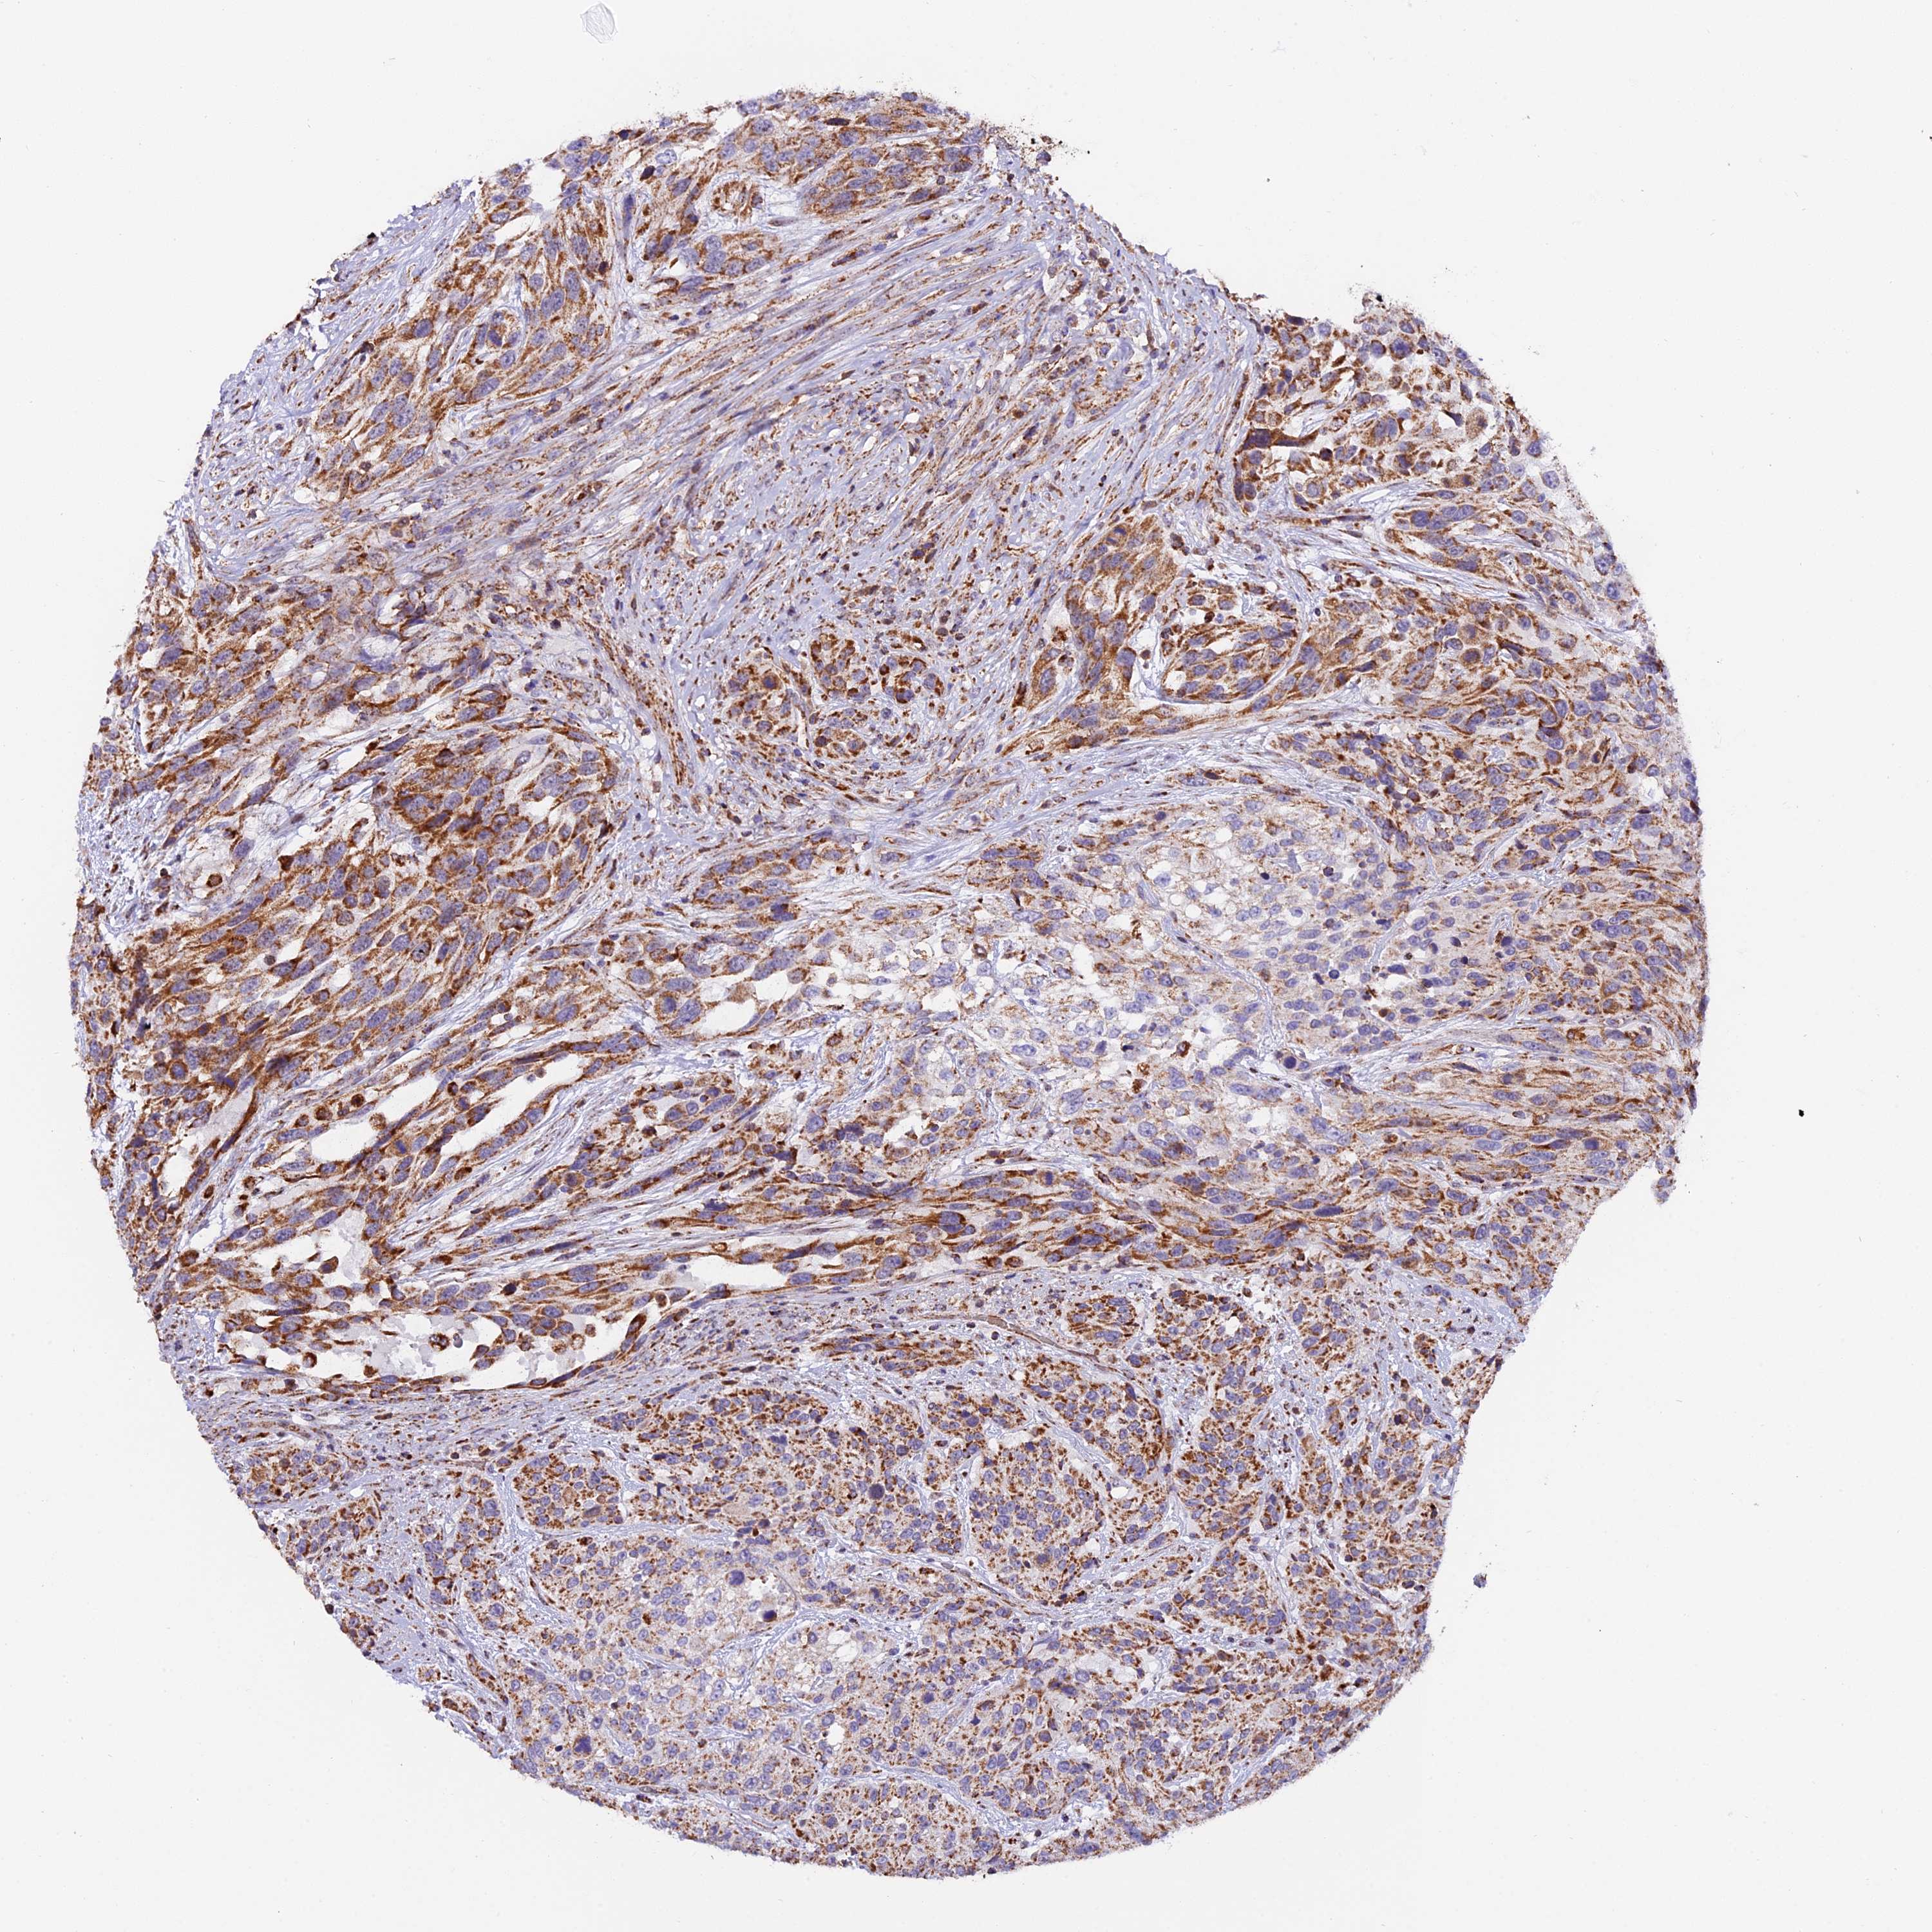

UROTHELIAL CANCER - Protein expressioni

A mouse-over function shows sample information and annotation data. Click on an image to view it in a full screen mode. Samples can be filtered based on level of antibody staining by selecting one or several of the following categories: high, medium, low and not detected. The assay and annotation is described here.

Note that samples used for immunohistochemistry by the Human Protein Atlas do not correspond to samples in the TCGA dataset.

Antibody stainingi

Antibody staining in the annotated cell types in the current human tissue is reported as not detected, low, medium, or high, based on conventional immunohistochemistry profiling in selected tissues. This score is based on the combination of the staining intensity and fraction of stained cells.

Each image is clickable and will lead to virtual microscopy that enables deeper exploration of all samples and also displays staining intensity scores, fraction scores and subcellular localization as well as patient and tissue information for each sample.

Antibody HPA041510

Antibody HPA041600

Urothelial carcinoma, High grade